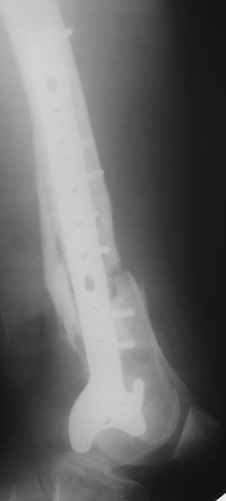

Обратился на консультацию больной. 24 декабря 2009г. попал в ДТП, получил переломы правого бедра, правой ключицы и левой голени. 28 января 2010г. выполнен металлоостеосинтез правой бедренной кости пластиной. 8 апреля 2010г. выявлен неполный перелом пластины, на половину, по одному из отверстий для винтов. 15 апреля 2010г., на фоне сепсиса, выполнен реостеосинтез со свободной костной аутопластикой зоны перелома. Ранний послеоперационный период осложнился нагноением гематомы в месте операции. Последняя была эвакуирована с сохранением фиксатора. Рана зажила. Через два месяца открылся свищ с незначительным слизисто-гнойным отделяемым, функционирует до сих пор без изменений. При осмотре – в центре послеоперационного рубца свищ, около 2 мм в диаметре, со скудным отделяемым. Зонд, введенный в свищевой ход, доходит до металлоконструкции. Коленный сустав отечный, активные и пассивные движения в нем резко ограничены и составляют: сгибание – 100 градусов, разгибание – 160. Выполнили рентгенографию – ложный сустав, остеомиелит, пластина установлена слишком низко, «внутрисуставно», что вызывает постоянный синовиит и отек параартикулярных тканей. Хотелось бы обсудить тактику дальнейшего лечения: 1. Считаем, что у молодого человека, милиционера по профессии, спасти коленный сустав другими способами, кроме БИОС, маловероятно. 2. Чему отдать предпочтение – обычный вариант или ретроградный? С уважением, Юрий Алексеевич Булахтин